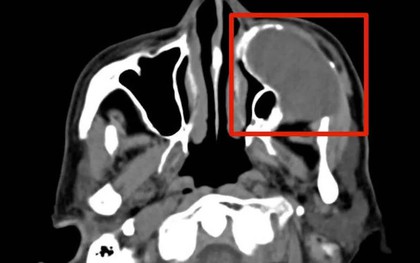

Sự chủ quan khiến khối u âm thầm ăn mòn ổ mắt

VTV.vn - Chủ quan với u nhầy xoang hàm nhiều năm, người bệnh 76 tuổi nhập viện khi khối u ăn mòn xương, xâm lấn sàn ổ mắt, đe dọa thị lực và gây biến dạng khuôn mặt.